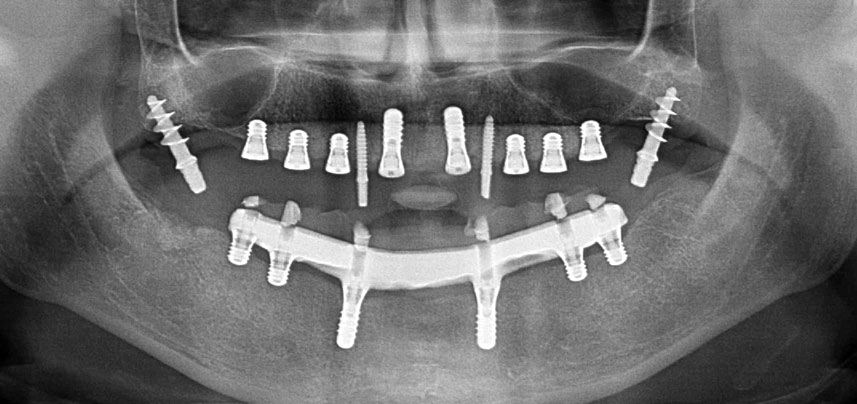

Trois ans après, le moment était venu pour elle de se doter d’une prothèse maxillaire du même type. Sur la base de la planification CBCT, l’élévation sinusale a été évitée grâce à la pose d'implants courts, et un gabarit chirurgical a été utilisé pour transférer les positions planifiées sur la crête alvéolaire (Figures 1 et 2).

Compte tenu de la dureté relative de l’os (D2) à cet endroit, les sites recevant des implants de 10mm de long aux régions 11 et 21 ont été finalisés à l'aide d’une fraise de 4mm de diamètre, associée à un contre-angle chirurgical W&H WS-75 L, au moteur d'implantologie Implantmed de W&H ainsi qu’au module Osstell ISQ de W&H. En revanche, en raison de leur structure osseuse molle, les sites postérieurs ont été préparés en vue de l’obtention d’un diamètre final de 3mm à l'aide de l’insert Piezomed I3P. Les implants ont enfin été posés par voie transgingivale (Flap Less) pour obtenir l’ostéointégration dans un délai de trois mois (Figures 6-10). L'appareil existant a été maintenu sur quatre implants provisoires (Fig. 8).